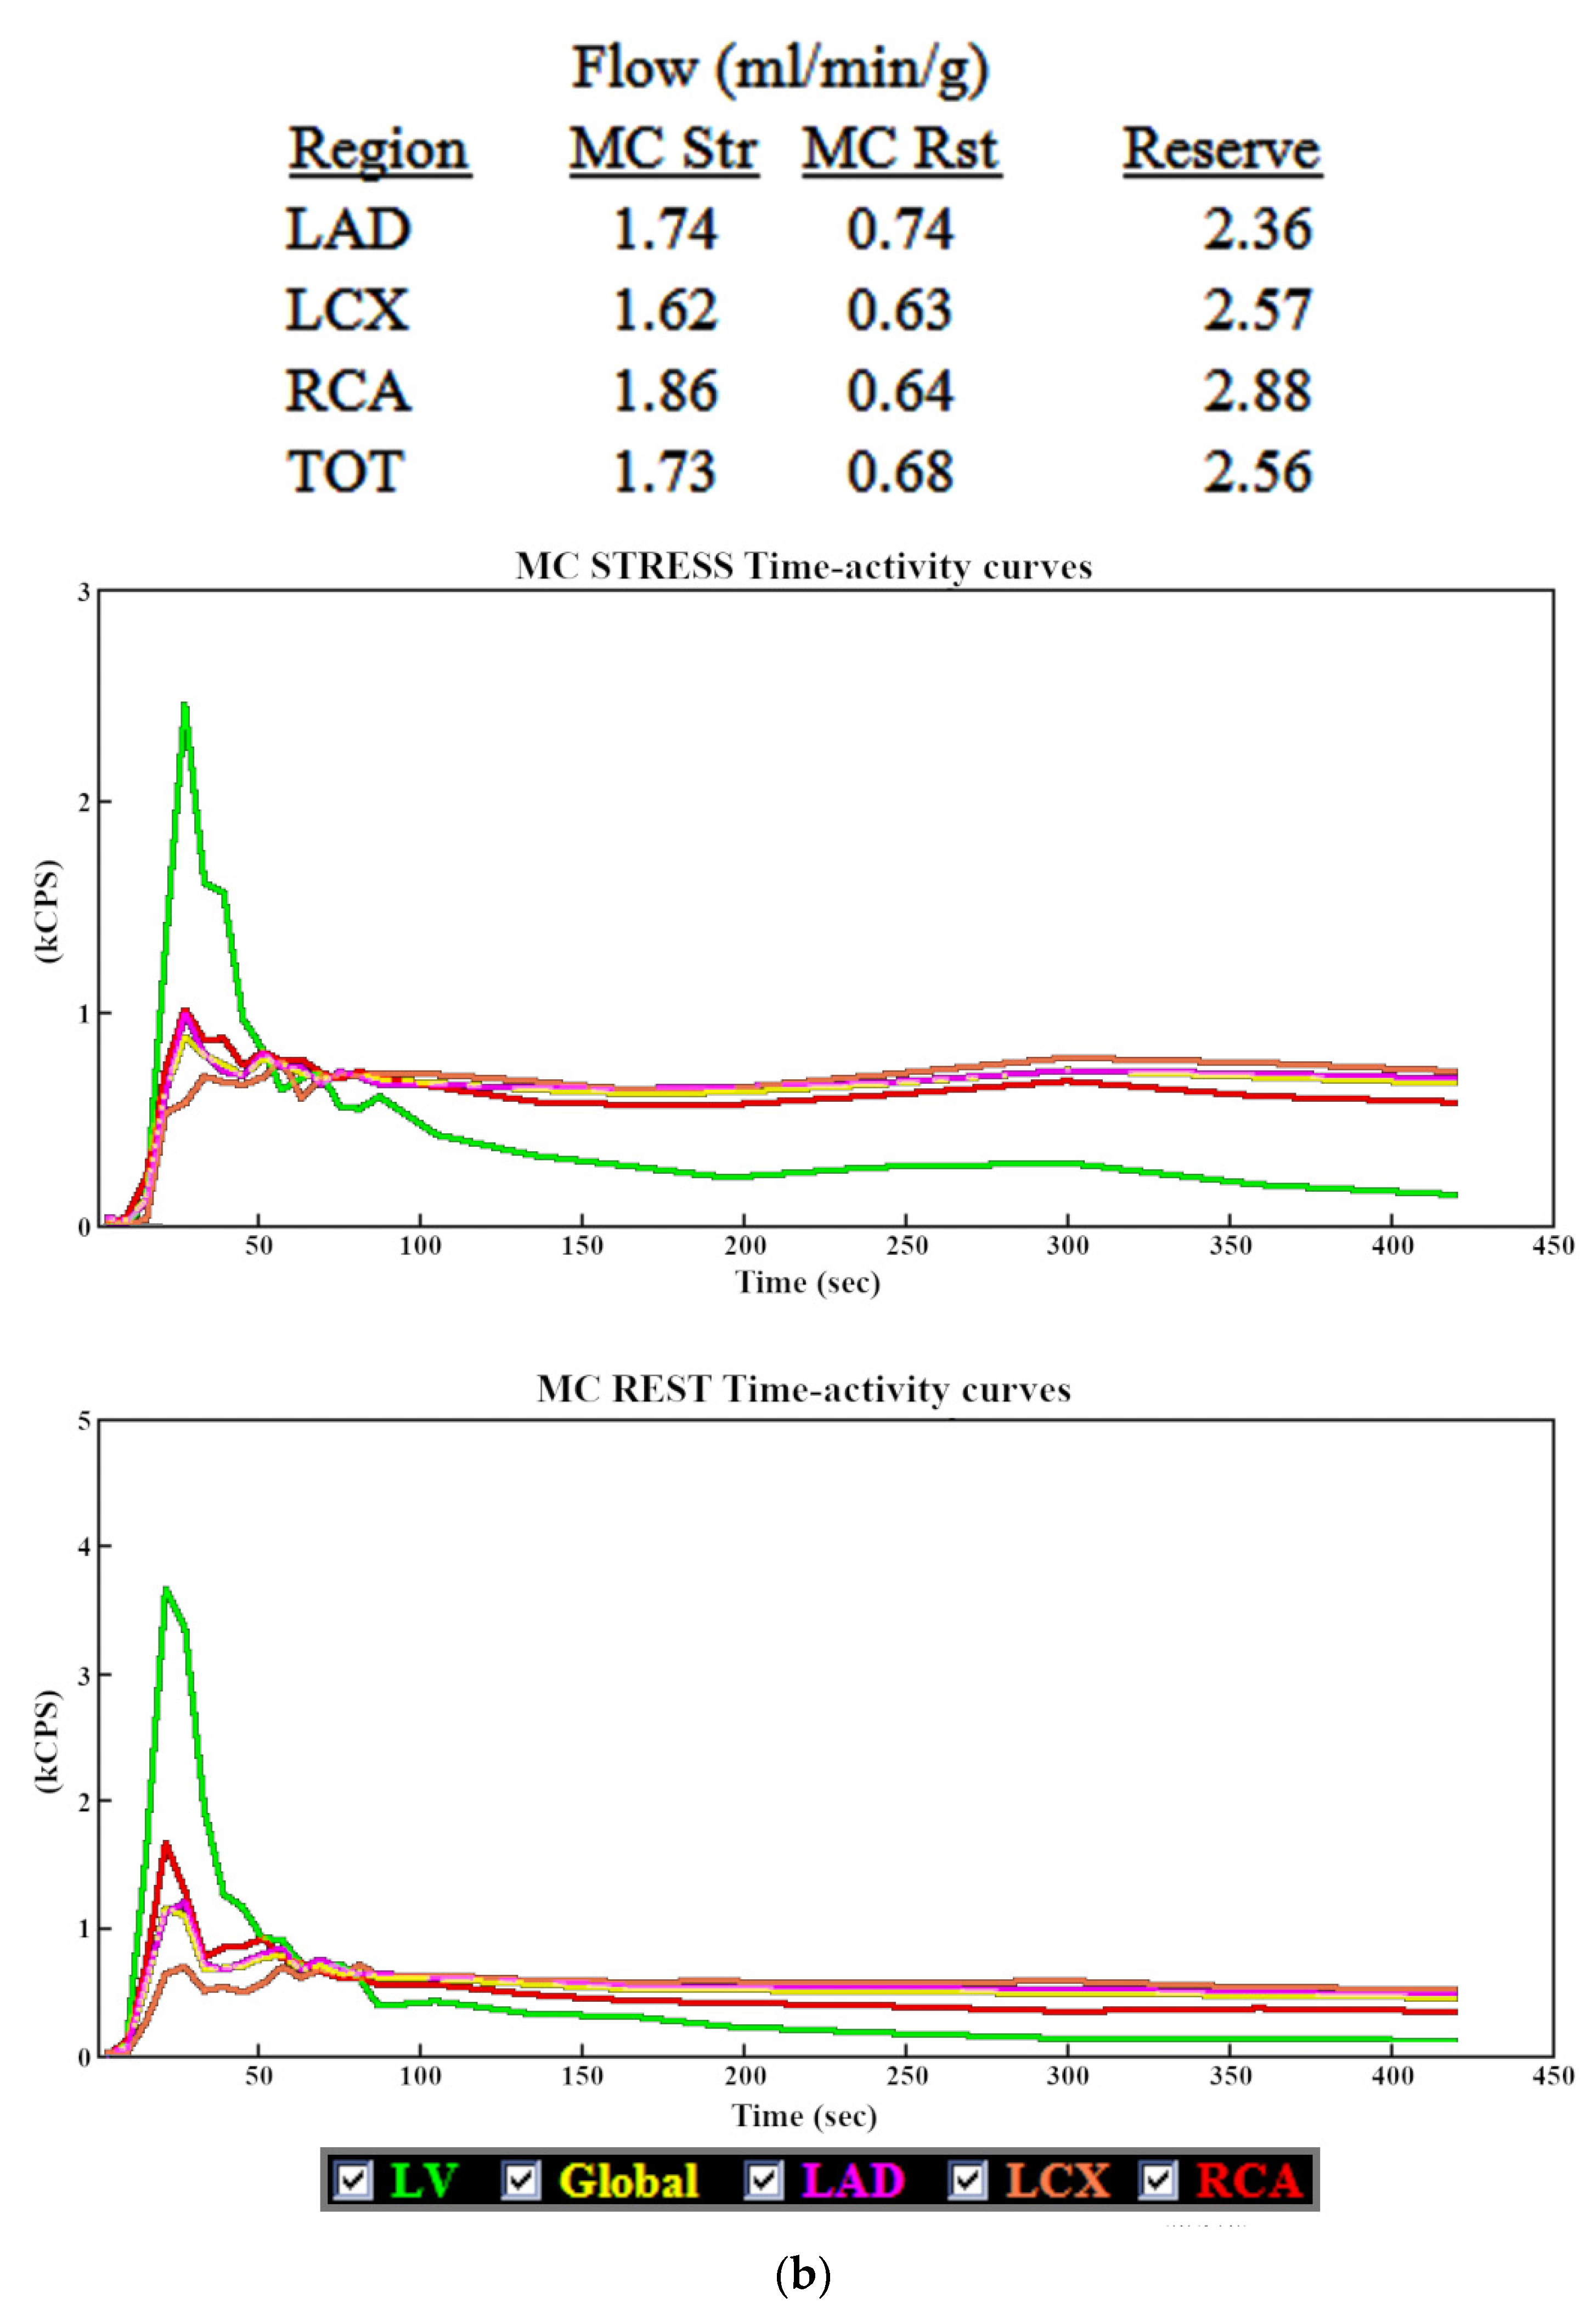

3.1. Myocardial Blood Flow

3.2. Myocardial Flow Reserve